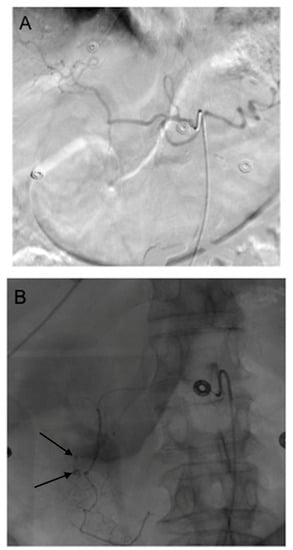

3. GDA Embolization in Gastrointestinal Bleeding

4. GDA Pseudoaneurysm Embolization

5. Pre-Y-90 GDA Embolization